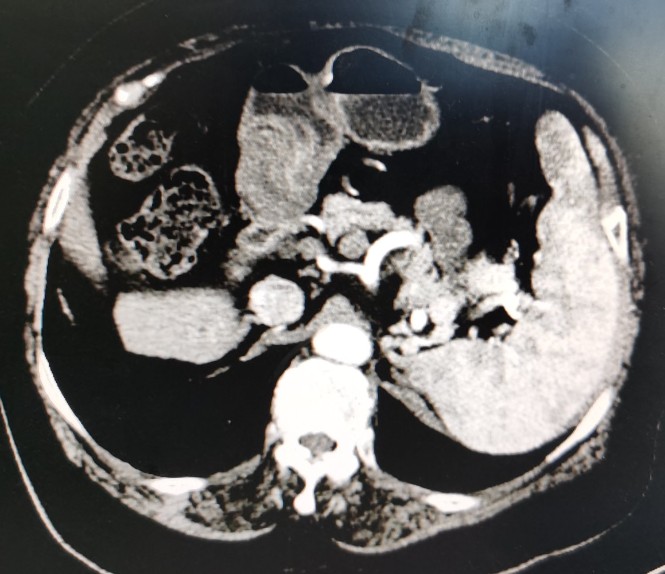

栓塞后复查的CT

栓塞后CT

肿瘤栓塞良好